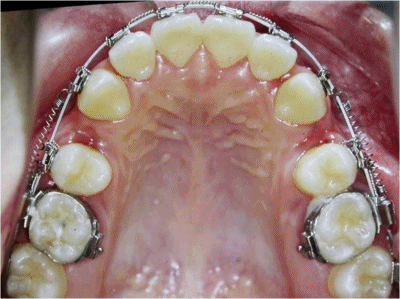

[感謝患者提供照片]